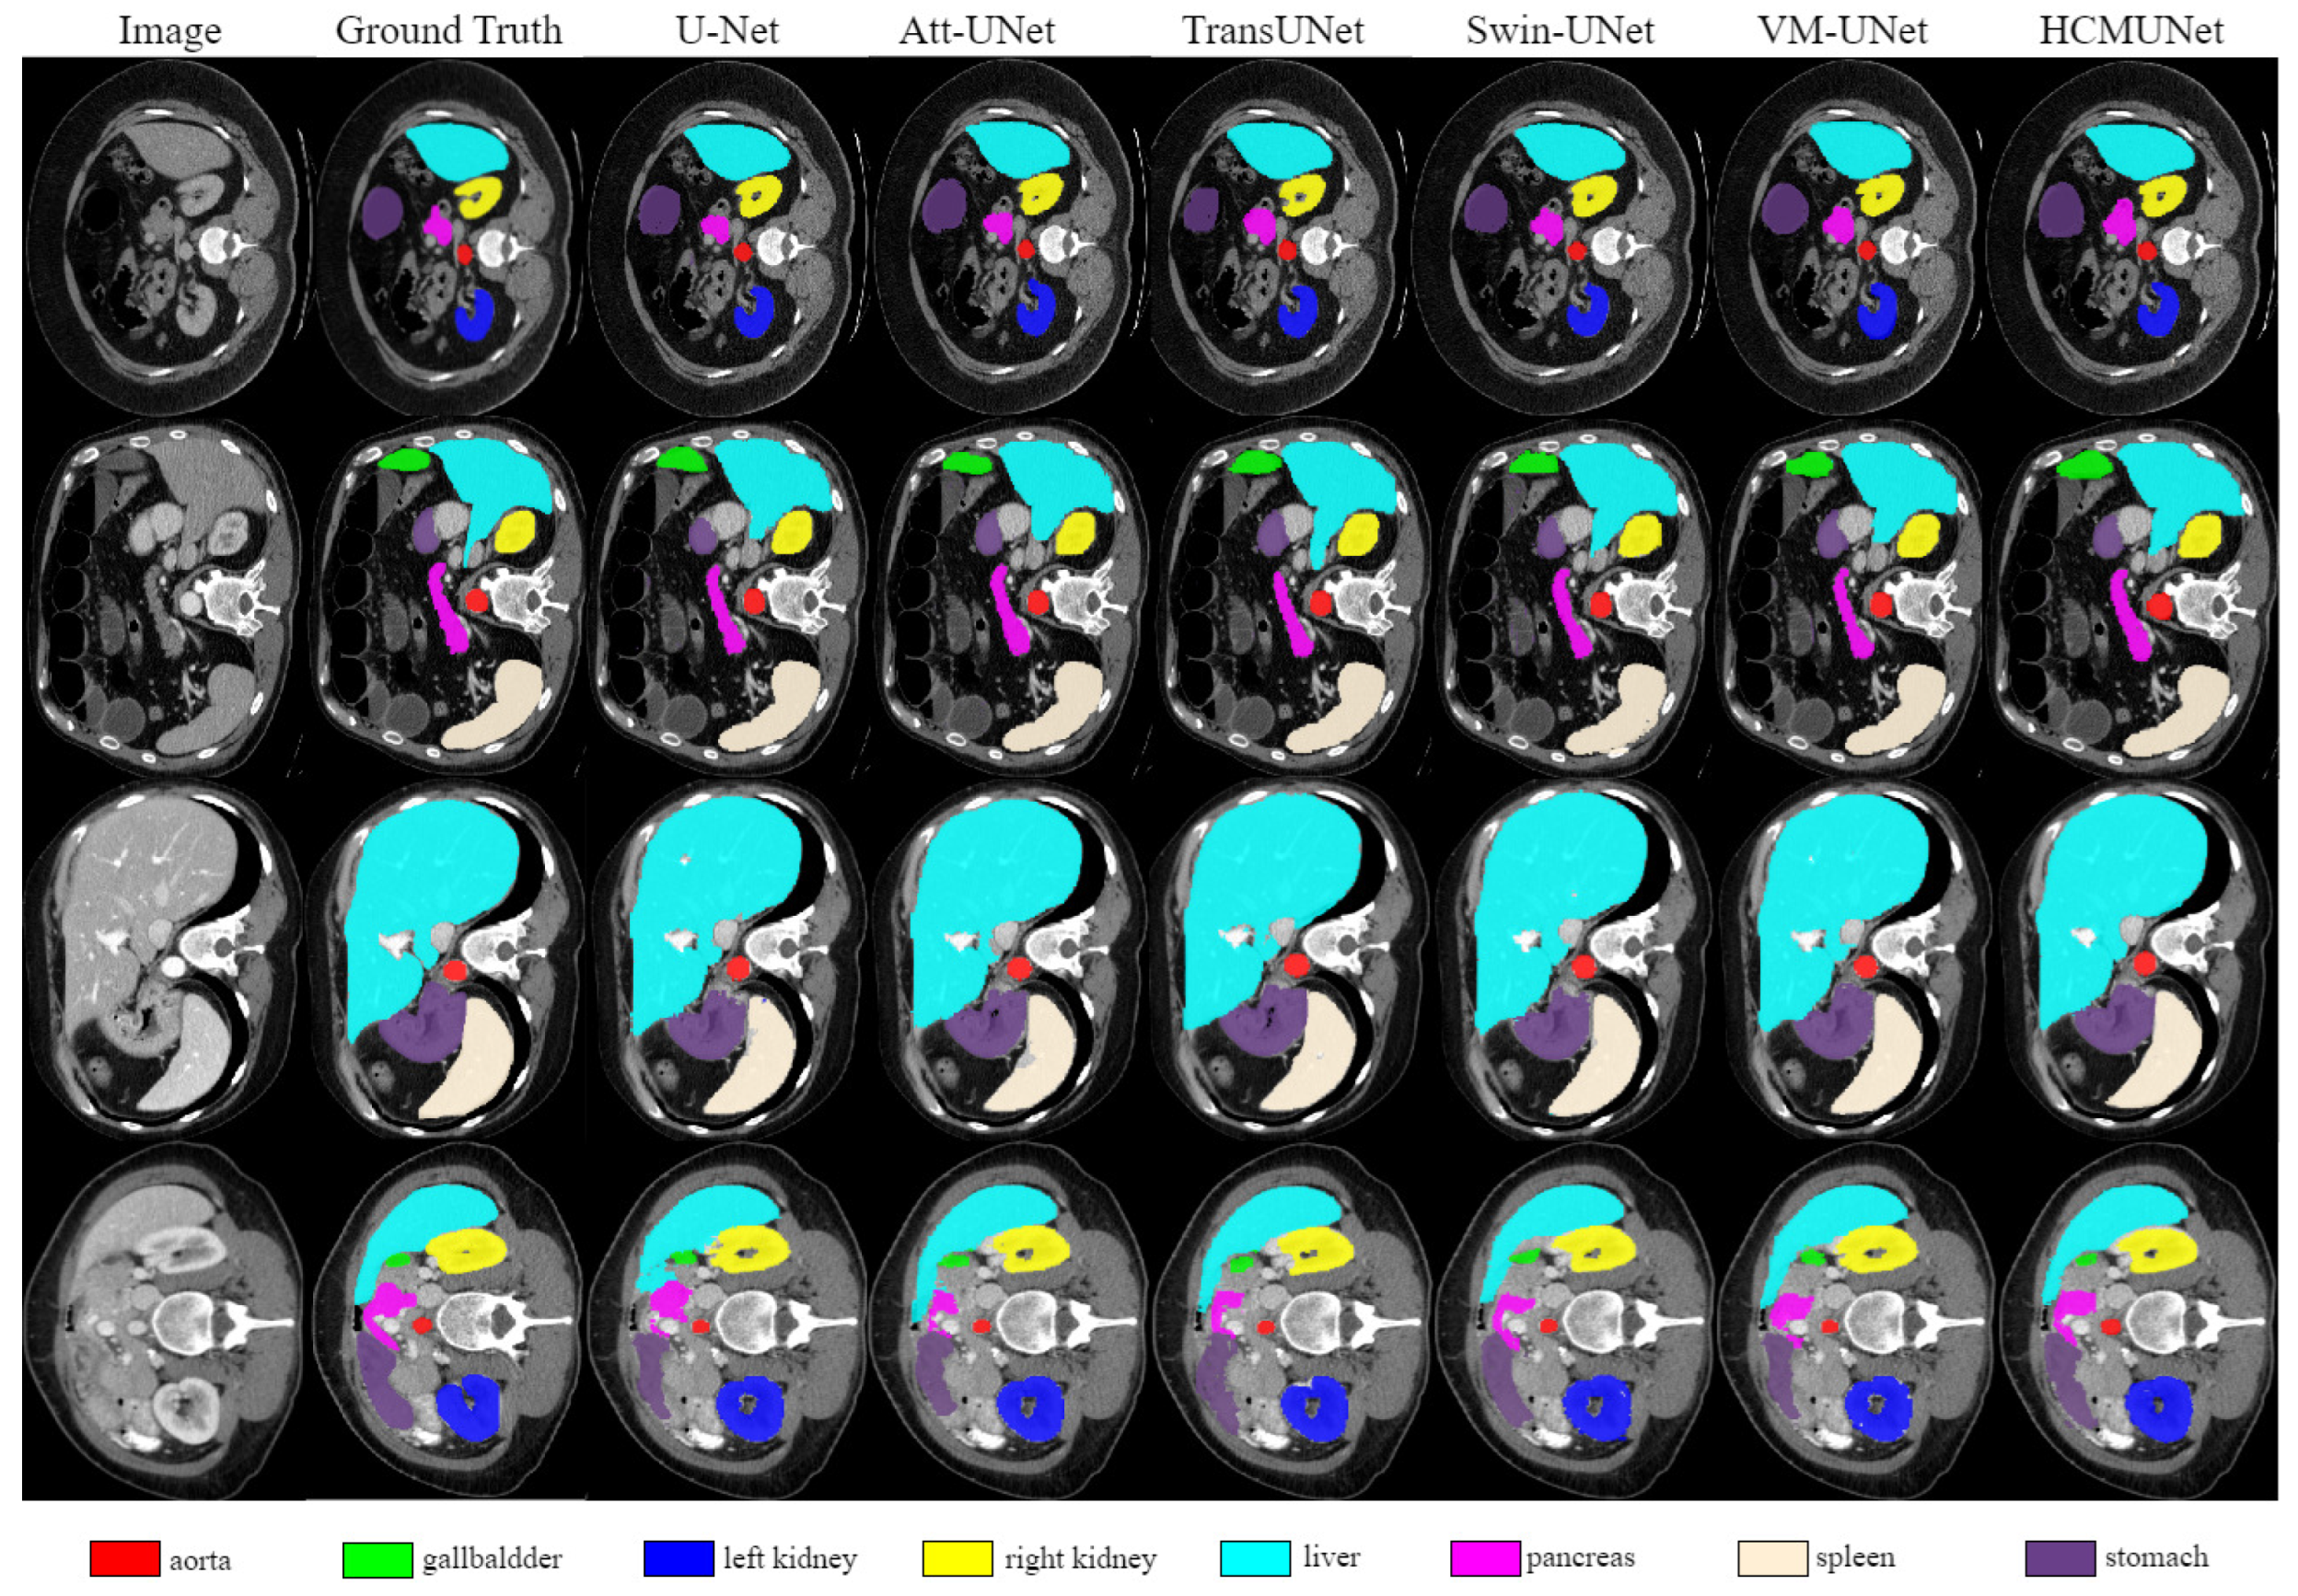

| Model | DSC | HD95 | Aorta | Gallbladder | Kidney (L) | Kidney (R) | Liver | Pancreas | Spleen | Stomach |

|---|---|---|---|---|---|---|---|---|---|---|

| U-Net [2] | 75.92 ± 2.71 | 37.55 ± 4.80 | 87.39 ± 2.87 | 67.52 ± 3.11 | 78.72 ± 2.04 | 68.87 ± 3.19 | 92.45 ± 1.26 | 51.51 ± 3.60 | 86.09 ± 3.67 | 74.82 ± 2.08 |

| Att-UNet [19] | 76.14 ± 3.32 | 33.51 ± 3.17 | 88.61 ± 2.12 | 66.40 ± 2.44 | 77.12 ± 1.49 | 71.07 ± 1.41 | 91.78 ± 2.43 | 55.01 ± 3.61 | 85.66 ± 2.72 | 73.47 ± 2.46 |

| TransUNet [43] | 76.46 ± 1.80 | 29.32 ± 4.27 | 86.55 ± 1.69 | 61.65 ± 3.40 | 79.41 ± 2.41 | 76.30 ± 2.95 | 93.13 ± 1.33 | 55.30 ± 3.29 | 84.63 ± 3.43 | 74.72 ± 1.87 |

| UCTransNet [45] | 78.24 ± 1.77 | 26.35 ± 1.38 | 86.52 ± 3.13 | 65.23 ± 2.05 | 80.69 ± 1.61 | 73.19 ± 2.58 | 93.05 ± 1.62 | 57.07 ± 2.65 | 87.55 ± 1.05 | 77.28 ± 2.48 |

| LeViT-UNet [46] | 78.82 ± 3.99 | 18.89 ± 3.99 | 85.23 ± 3.73 | 66.32 ± 1.39 | 82.68 ± 3.33 | 78.13 ± 3.37 | 93.61 ± 1.80 | 60.95 ± 2.50 | 89.00 ± 1.56 | 74.62 ± 3.68 |

| Swin-UNet [26] | 79.19 ± 2.07 | 22.07 ± 2.67 | 84.72 ± 2.61 | 66.60 ± 3.40 | 82.82 ± 1.19 | 79.41 ± 0.68 | 93.94 ± 0.75 | 59.49 ± 3.67 | 89.21 ± 2.31 | 77.36 ± 1.22 |

| HiFormer [47] | 80.55 ± 2.19 | 15.63 ± 3.41 | 87.07 ± 2.24 | 66.67 ± 2.27 | 83.92 ± 2.24 | 81.09 ± 2.91 | 94.09 ± 1.84 | 60.17 ± 2.72 | 90.76 ± 1.74 | 80.61 ± 2.31 |

| VM-UNet [12] | 80.47 ± 1.71 | 18.91 ± 2.42 | 86.84 ± 1.59 | 68.43 ± 4.13 | 85.04 ± 2.16 | 81.12 ± 2.67 | 94.11 ± 0.48 | 59.49 ± 1.78 | 87.77 ± 3.16 | 80.97 ± 2.33 |

| EMCAD [48] | 81.16 ± 2.01 | 16.72 ± 4.44 | 85.24 ± 1.80 | 67.24 ± 4.64 | 87.62 ± 0.30 | 81.38 ± 0.91 | 94.67 ± 1.77 | 61.02 ± 3.96 | 91.81 ± 2.35 | 80.30 ± 1.93 |

| HCMUNet (Ours) | 81.52 ± 1.14 | 17.83 ± 1.47 | 88.06 ± 1.63 | 69.60 ± 2.30 | 87.04 ± 0.67 | 82.35 ± 1.48 | 95.10 ± 3.71 | 59.24 ± 3.62 | 90.63 ± 1.54 | 80.76 ± 2.30 |